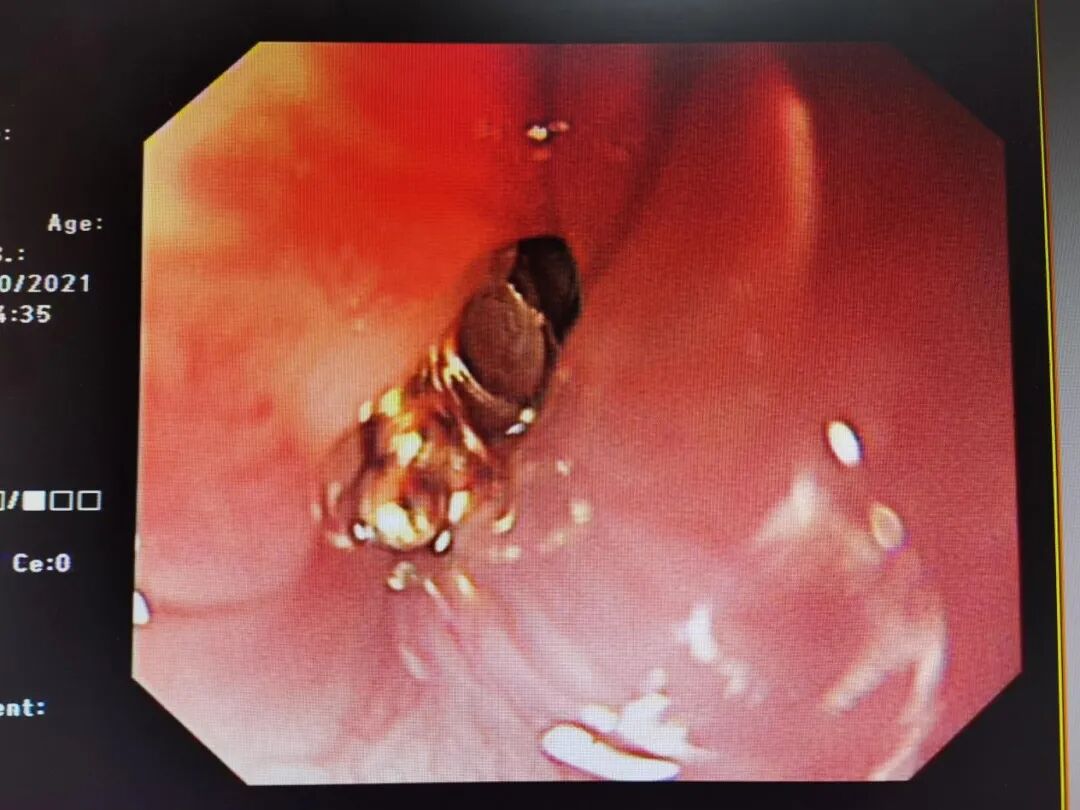

▲图丨胃镜下可见金属异物卡在食管上段

手术由消化内科经验丰富的买买提吐尔逊医生进行。“胃镜刚进入10cm就看见金属异物卡在食管上段,但小宝宝哭闹太厉害,异物钳无法打开。退镜后我们立即改变策略,给胃镜头端安装辅助的透明帽,重新进镜再尝试用异物钳,最终成功将异物取出。”买买提吐尔逊医生介绍道。